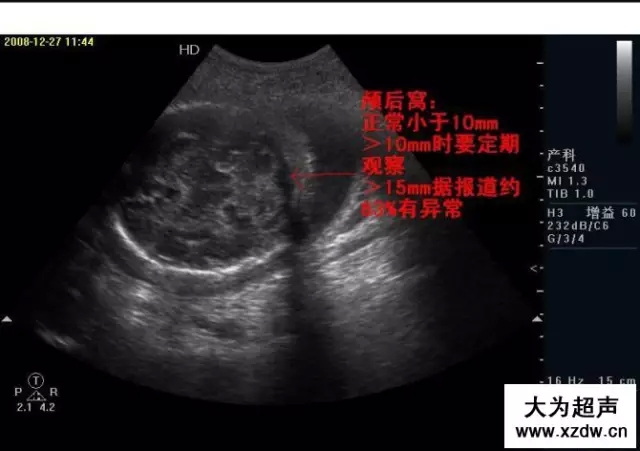

產(chǎn)科超聲正常圖片